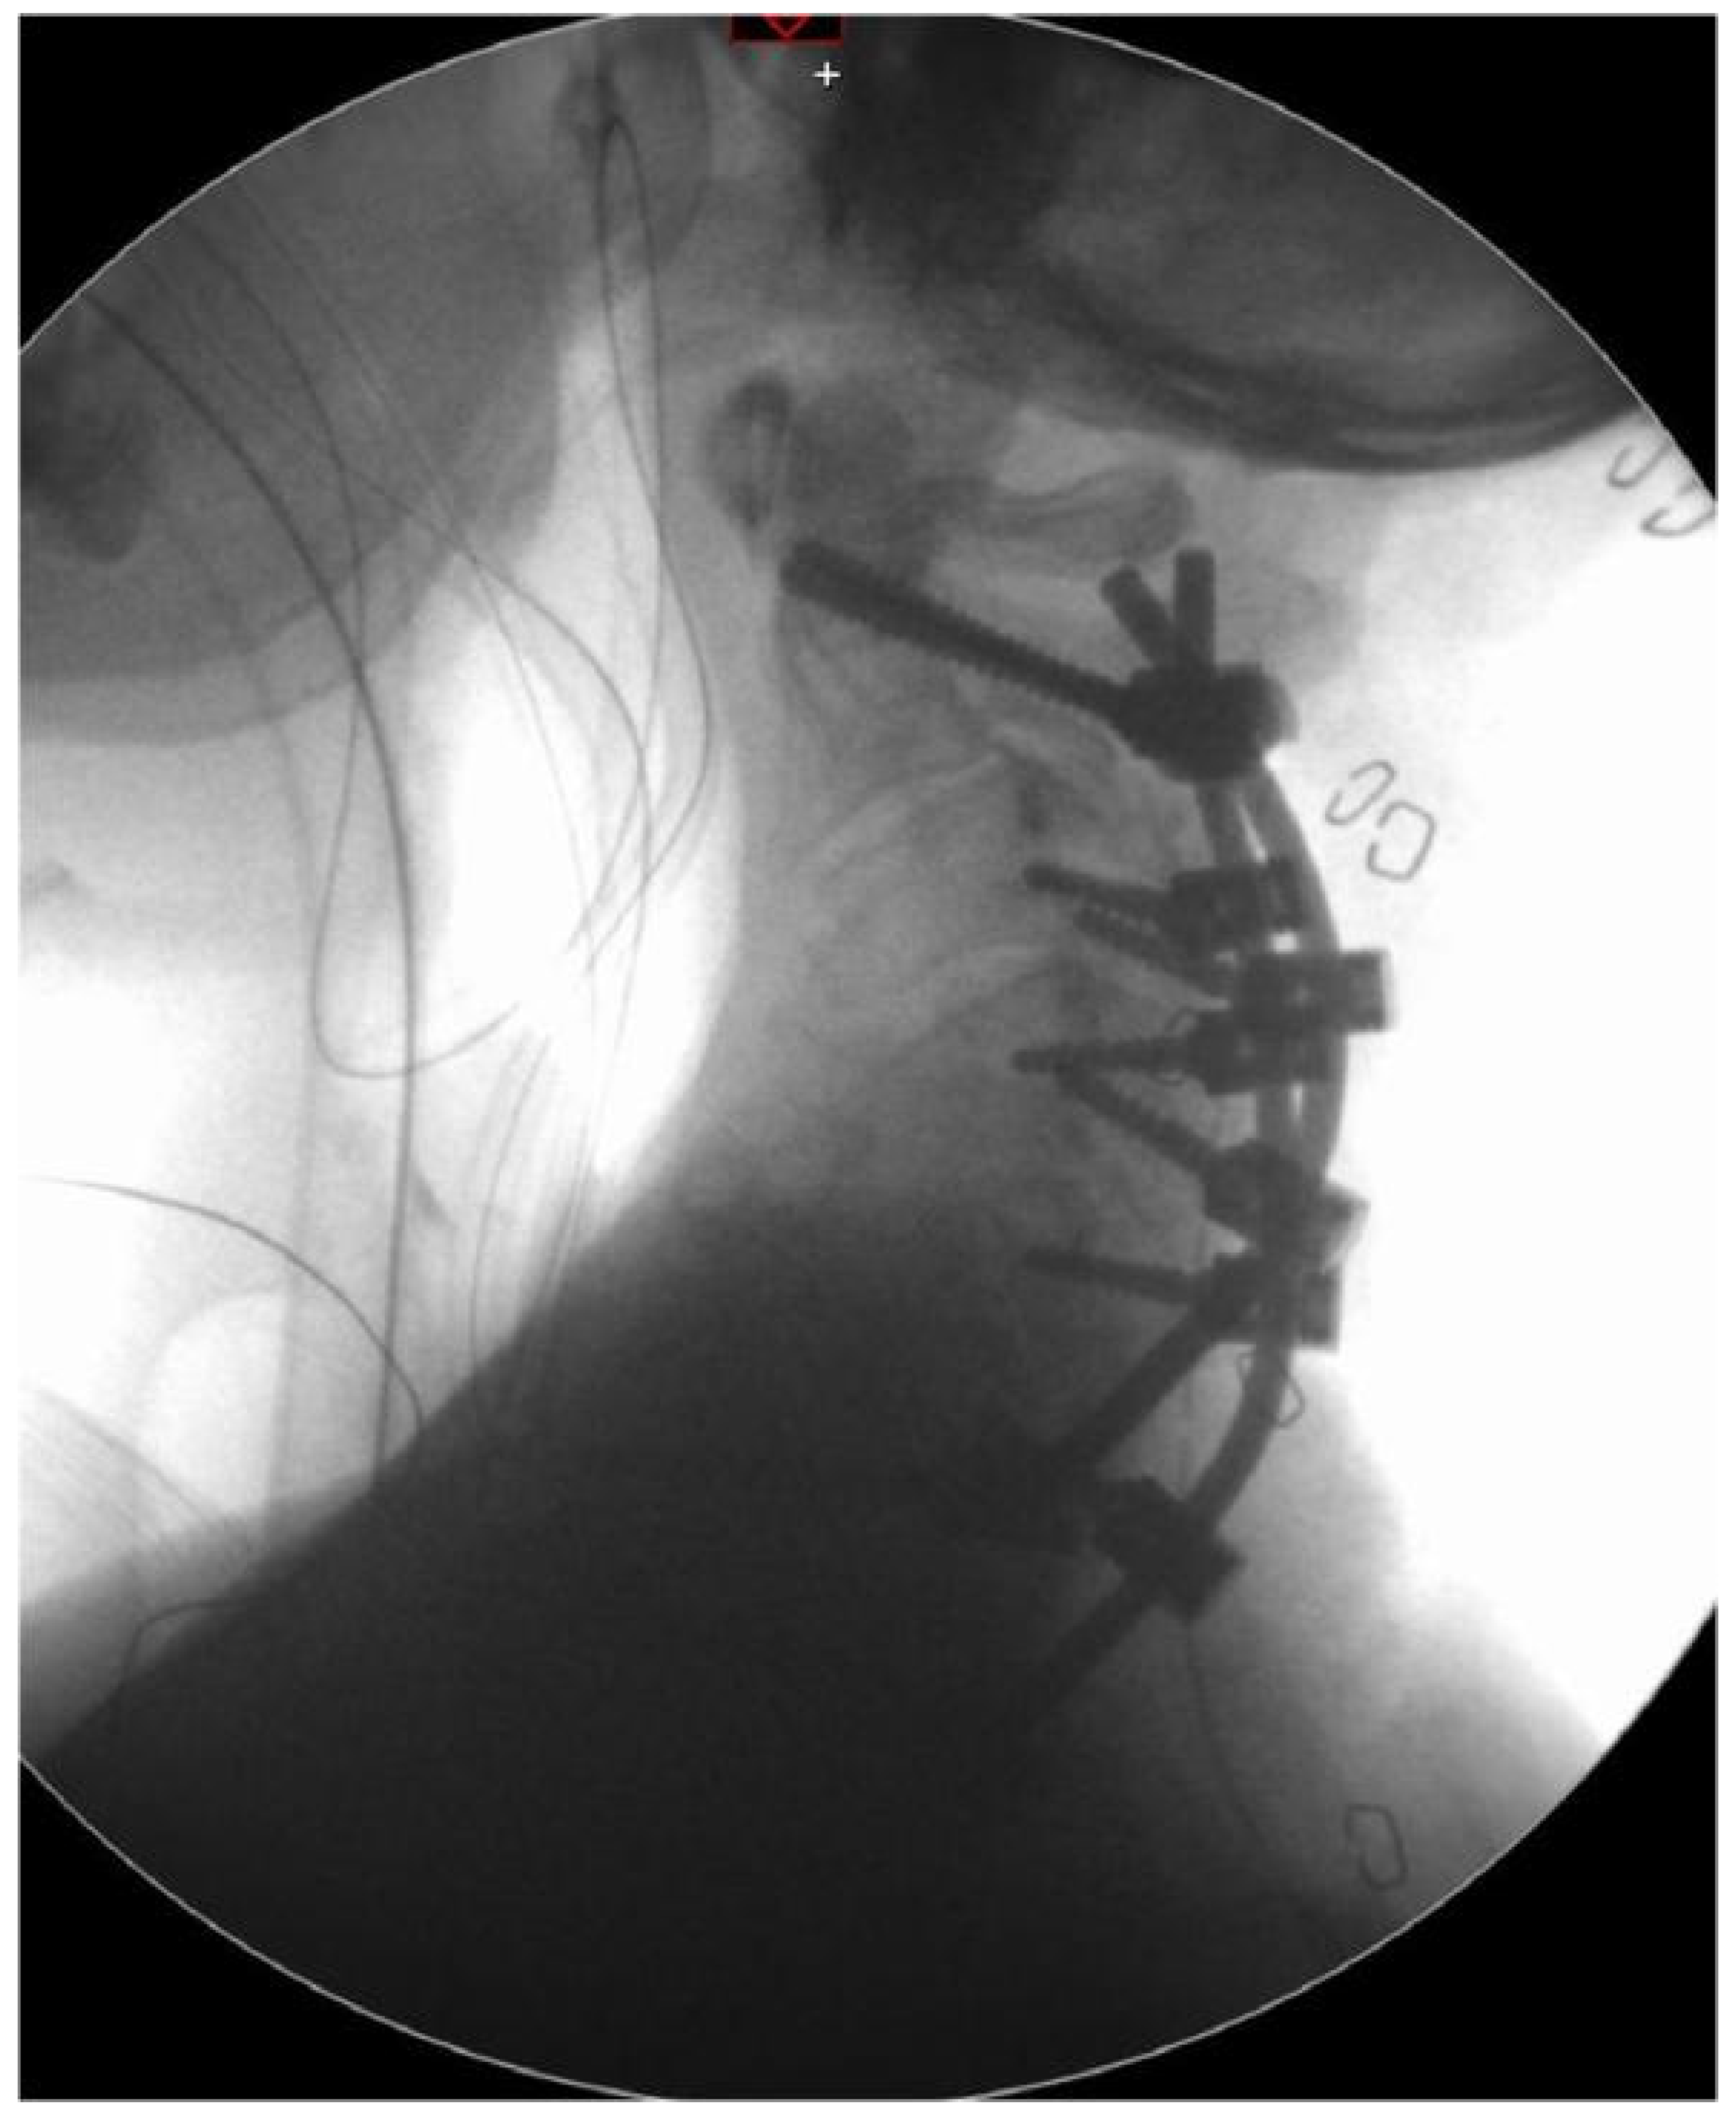

Figure 1.

Medical imaging of pre-operative cervical spine: sagittal view from 3D virtual rendering from CT DICOM viewer (left) and MRI scan (right). In the latter, the third (C3) and fifth (C5) cervical vertebrae are indicated by arrows.

Preoperative MRI showed a severe compression between C3 and C5 (Figure 1) and confirmed the severe kyphosis (60° between C2 and C6) and scoliosis (40° left cervical curve). Therefore, the patient was enrolled for posterior decompression and fixation surgery. Because of the severe deformation of the vertebral elements (articular masses, pedicles, vertebral bodies) associated with the deformity, it was understood that it would have been very challenging to safely place the metal hardware (screws and roads) in the right position, which also was very close to vital structures such as the spinal cord and vertebral arteries. Informed consent was obtained from the patient in order to use anonymized radiological imaging for scientific purposes.